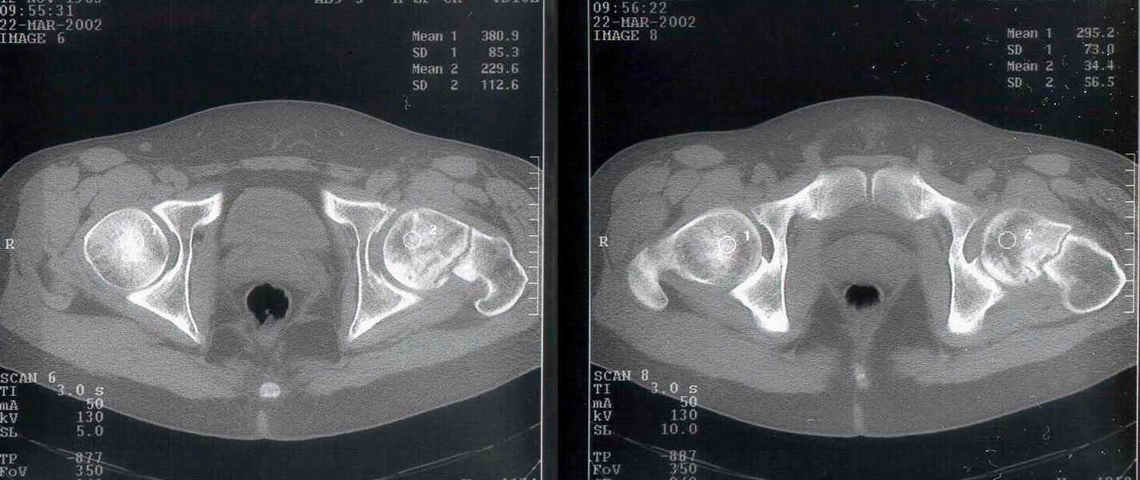

Уважаемый Александр! По 38-летнему пациенту. На томограмме имеются явные признаки асептического некроза. Этот процесс будет развиваться стремительно.

1-2 года и Вы вынуждены будете эндопротезировать пациента. Есть ли необходимость в дополнительной операции (остеотомии)? У 35-летнего пациента

альтернативы нет. Протез. АИФ.

Коль скоро функция сустава сохранена, я бы не торопился с эндопротезированием у 38 летнего пациента.

Рентгенологические признаки пост травматического аваскулярного некроза по классификации Ficat / Arlet Stage 1. на мой взгляд DHS - без какой -либо остеотомии стабилизировало зону перелома, а сам процесс рассверливания шейки бедра съимитировал бы так называемую core decompression procedure, которая показана при 1-3 стадиях AVN.

At first is necesary take a Magnetic Resonance for the diagnosis de avascular necrosis.

I see zones of osteoporosis in the head and for this is necesary a vascular existence, then for me was necesary the MR.

You have a non union neck, avascualr necrosis and varus deformity.